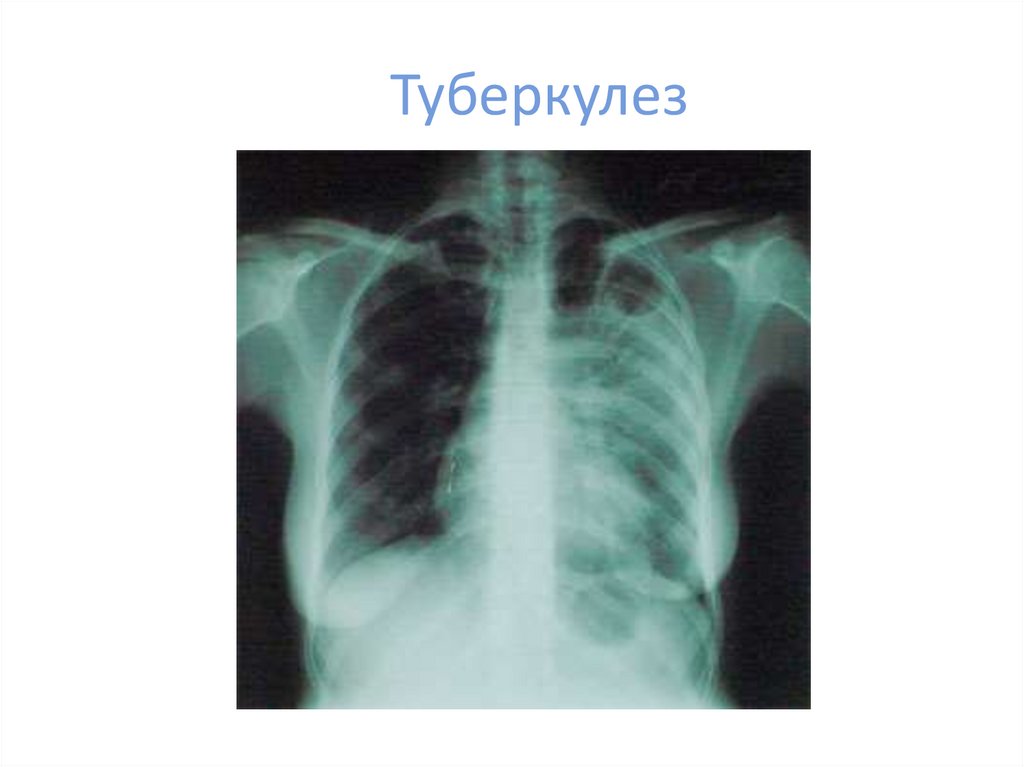

Туберкулез

многие другие заболевания

• Туберкулез